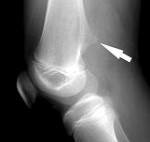

Диагноз выставляется на основании совокупности клинических и рентгенологических признаков. При этом решающую роль в постановке окончательного диагноза обычно играет рентгенография. Иногда в качестве дополнительных методов исследования также используется магнитно-резонансная томография и компьютерная томография.

На рентгенограммах выявляется изменение контуров кости, обусловленное наличием опухолевидного образования, связанного с основной костью широкой и толстой ножкой. Поверхностные отделы образования имеют неровные контуры и по своей форме могут напоминать цветную капусту. В отдельных случаях ножка отсутствует, и остеохондрома прилегает к «материнской» кости. Контуры остеохондромы четкие, непрерывные, непосредственно переходящие в контуры основной кости.

Хрящевая шапочка на рентгеновских снимках обычно не определяется за исключением случаев, когда в ней есть очаги кальцификации. Поэтому не следует забывать, что реальный диаметр остеохондромы может на 1-2 см превышать диаметр, определяемый по данным рентгенографии. При подозрении на увеличение размеров хрящевой шапочки необходимо проведение магнитно-резонансной томографии.